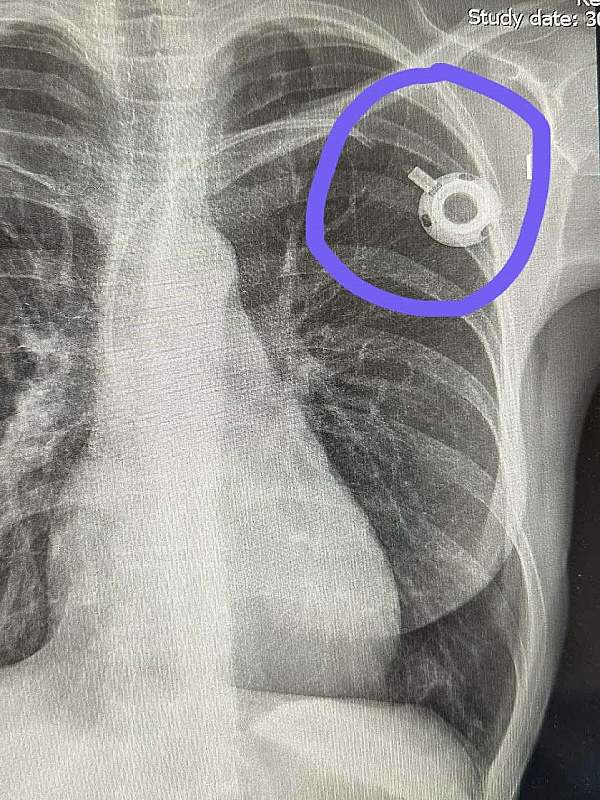

Port za hemoterapiju, mali implatant, koji se ugrađuje na veliku venu ispod ključne kosti, odavno je standard u svetu u lečenju onkoloških i drugih teških pacijenata. Port se u svim evropskim i svetskim centrima uvodi rutinski za lečenje. I kod odraslih, i kod dece, bez centralnog venskog pristupa (port), ne započinje se terapija, pogotovo ako je planirana višemesečna terapija. Od 2000-e godine port postaje rutinska medicinska praksa u razvijenim evropskim zemljama sa jasnim protokolima, standardima sterilnosti i obučenim timovima. 1982. godine prvi komercijalni Port-a-Cath ulazi u široku kliničku upotrebu u SAD, i to je prelomni trenutak početka njegove upotrebe. Mnogo pre toga, razvija se koncept venskog porta, pre svega da nema cevi van tela, da smanji infekcije i da pacijent lakše podnosi terapiju i živi između tih terapija. njegovi benefiti su višestruki. Više od 40 godina kliničkog iskustva učinile su da port i danas traje. Iako je u Srbiji on novina odnedavno, ta mala spravica nije nikakav novi eksperiment niti luksuz, niti novitet u lečenju, već standard rutinske upotrebe u svetu i Evropi.

O Ugradnji Porta